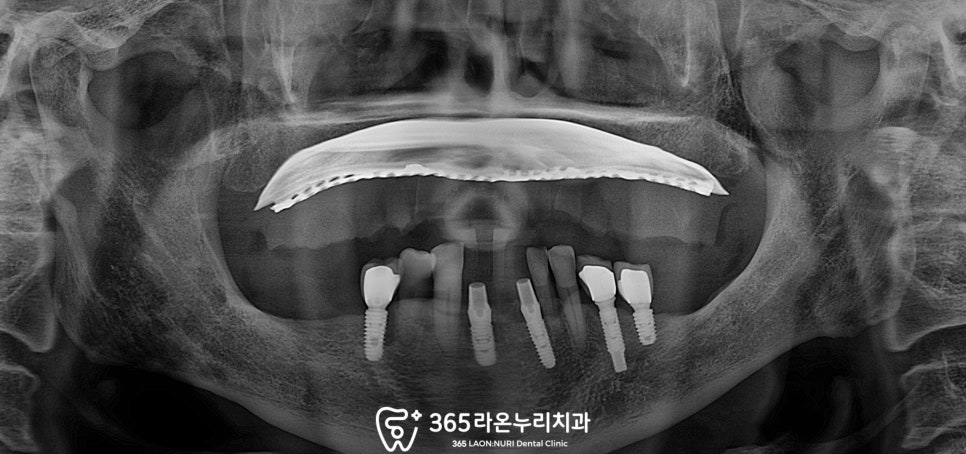

이번 케이스에서도 마찬가지로

#31,41,42 하악 전치부 3개의 치아가

상실되었지만 픽스처는 #31,42 자리에

두 개만 심고 브릿지 형태로

심미성을 되찾기로 합니다.

3~4개월 정도 기다린 뒤

인상채득(본뜨기) 및 보철 세팅을

진행하고, 몇 개월간 앞니 부분을

비워둘 순 없었기 때문에

기성 어버트먼트에 임시치아를

사용하도록 합니다.